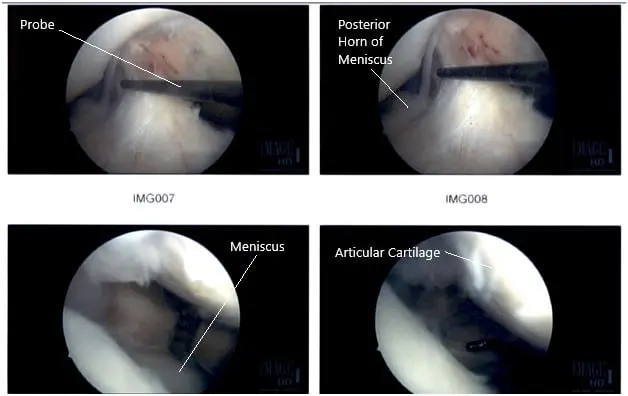

Intraoperative Arthroscopic Images of the right knee.

The lateral meniscal tear was further debrided and the final pictures were taken. At the end of the procedure, a micro punch was also used to put 4 to 5 holes into the intercondylar area. Fat globules and fresh blood could be seen coming out of those holes. The knee was irrigated copiously and closed using nylon #4-0. The dressing was done.